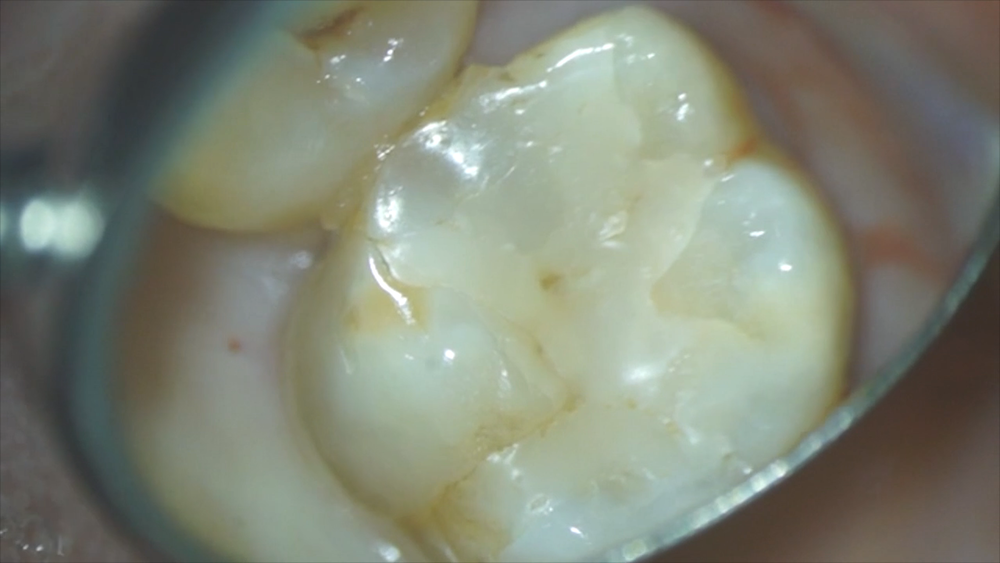

術前の写真です。手前の歯との間のつめ物であるコンポジットレジンに段差があり、患者さんも、ここに物がよくつまり、フロスが通らない、と言っていました。